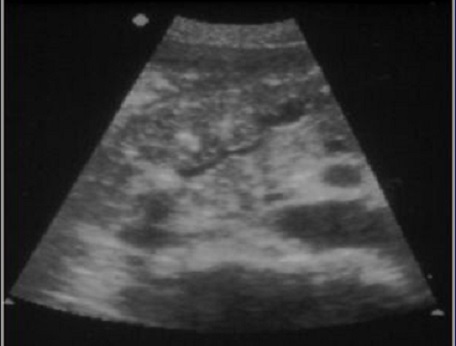

. Echographie :

Image echographique

percutanee direct de

pancreatite chronique est image de hyperechogene

heterogeneite de la

parenchyme pancreatique , sa taile peut augemente ,

normalement ou diminue sa bord est irregulier ,parfois

en presente des nodules calcification parenchymeteuse ou bien

image calcaire des calculs du canal pancreatique ce qui donne

de aspect de cone de l.ombre posterierure, en ce cas les

canal intra pancreatique sont dilates .

Les faux kyste associe peut en presente et se donne des images aechogene ou

hypoechogene intrapancreatique . Imge de ascite parfois se

en voyait